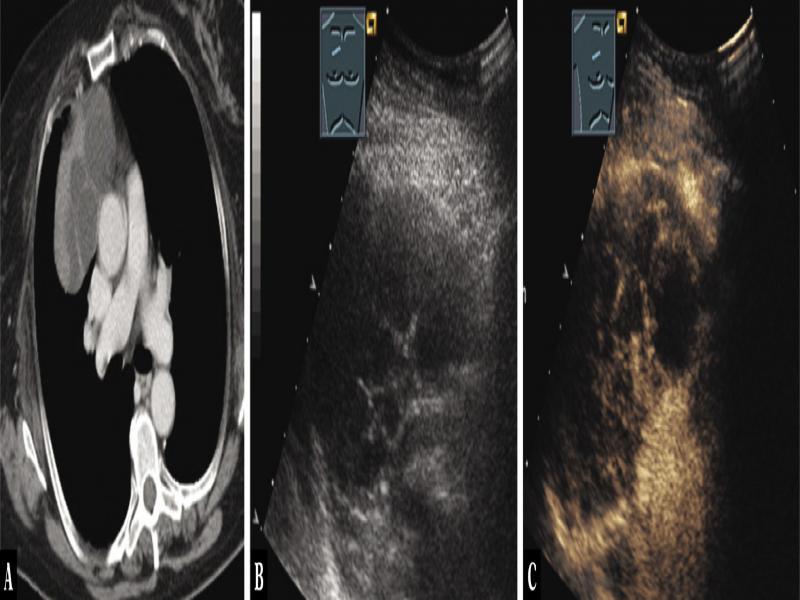

Fig. 10.

A 71-year-old male patient with dyspnea and a mass in the anterior mediastinum on computed tomography (A). Thoracic ultrasound indicated a complex hypoechoic tumor (B), which on contrast-enhanced ultrasound showed large areas with lack of enhancement, as in necrosis (N), and only marginal vital tissue (C). Ultrasound-guided-biopsy from perfused tissue was performed, and the diagnosis of bronchial carcinoma was confirmed histologically